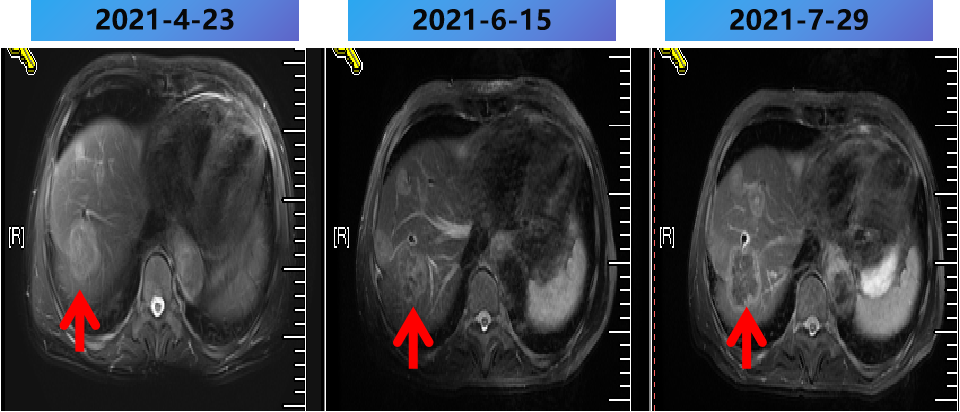

2021-2-25至2021-7-15 更换方案为bev+伊立替康+雷替曲塞 9周期,部分病灶稳定(SD)。

2021-2-25至2021-7-25 更换方案为bev+伊立替康+雷替曲塞 9周期,部分病灶PD。